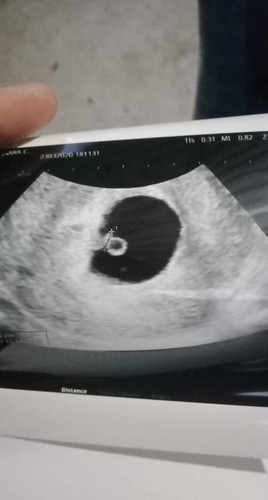

เจอเเล้วตัวน้อยของแม่ 6 สัปดาห์. กับ5. วัน หมอบอก หัวใจน้องเต้นแล้ว